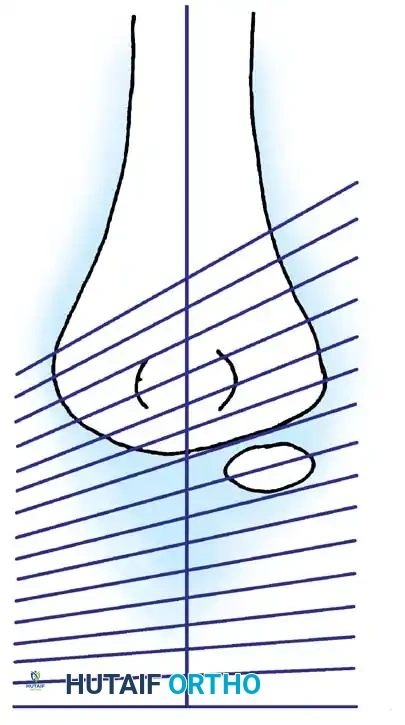

Fig. 33-36 Overcorrection with posterior convexity for anterior dislocation.

Fig. 33-37 Overcorrection with medial convexity for lateral dislocation.